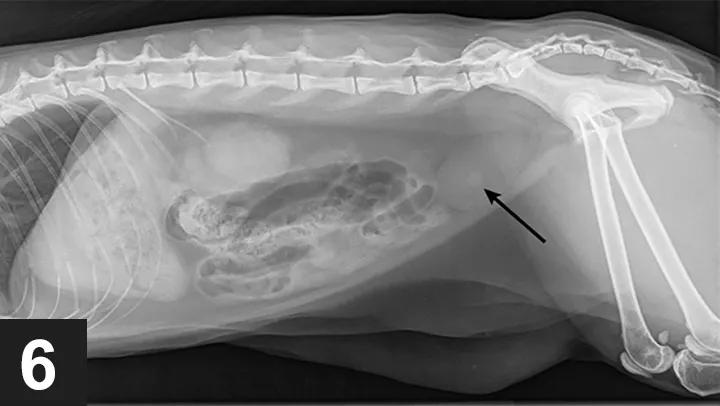

↑箭头标出的是尿结石

尿道梗阻也可能是尿道痉挛引起的肌肉收缩,或者由肿瘤、感染、外伤导致。此外,在一项研究中,特发性膀胱炎(FIC)的病因也占比过半。